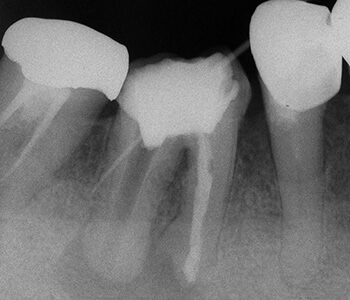

根の側壁に穴が開いて感染していることにより、前後の根の間の骨が吸収してなくなっています。

根の先端部分が著しく破壊しており、その周囲の骨もかなり吸収しています。